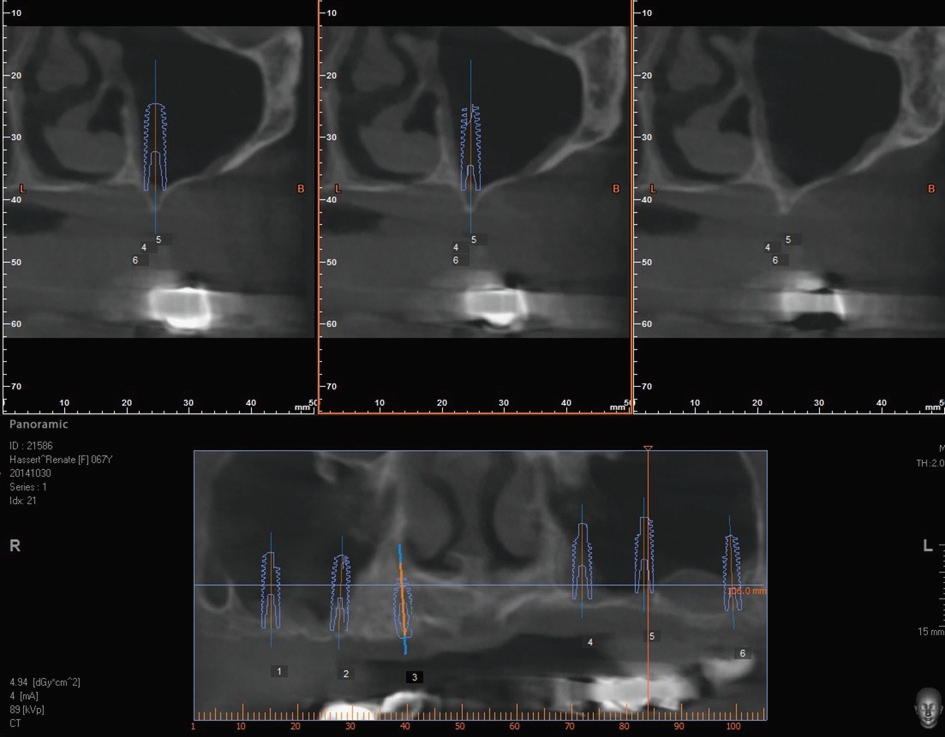

Vor dem zweiten OP-Eingriff nach 4 Monaten wurde im Labor eine Bohrschablone angefertigt. Zudem wurde ein DVT angefertigt, um im Sinne eines Backward planning die ideale Implantatposition planen zu können. Bei Eröffnung des augmentierten Kieferbereiches zeigte sich im augmentierten Bereich eine gute Regeneration und Revaskularisierung des Knochens (Abb. 14 bis 17). Sechs Implantate konnten somit in den augmentierten Bereich (Astratech EV®, DENTSPLY Sirona, Mannheim) mit ausreichender Länge und Durchmesser in Form einer gleichmäßigen Pfeilerverteilung in den Kieferknochen Inseriert werden (Abb. 18).